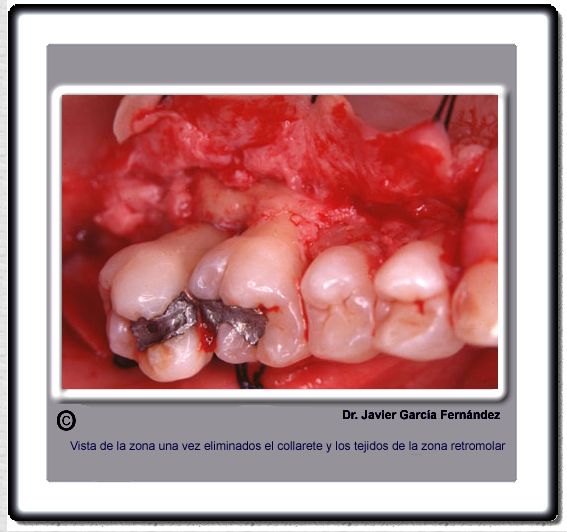

image 199